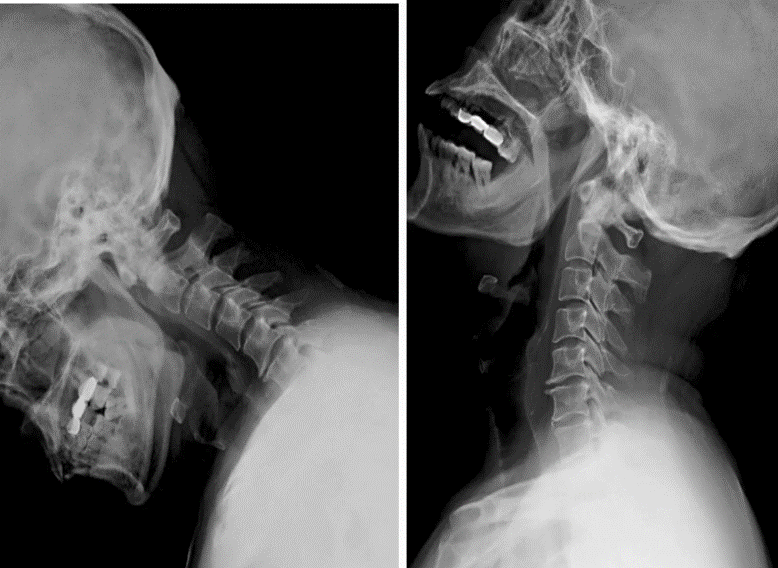

科室设置四个亚专业:创伤骨科以微创开展复杂骨折与多发伤救治,实现骨折愈合与功能恢复同步;手足显微外科凭精细显微操作,开展断指(肢)再植、血管神经损伤修复,游离皮瓣移植创面修复,各类手足畸形矫治;关节与骨质疏松组遵循阶梯化治疗,开展保关节、微创关节置换及各类关节翻修手术,骨质疏松专业实现骨质疏松全生命周期管理,规范抗骨质疏松治疗切实降低骨折风险,改善骨质健康;运动医学专业以关节镜微创技术为核心,诊治各种运动系统损伤,结合康复疗法助力患者重返运动。